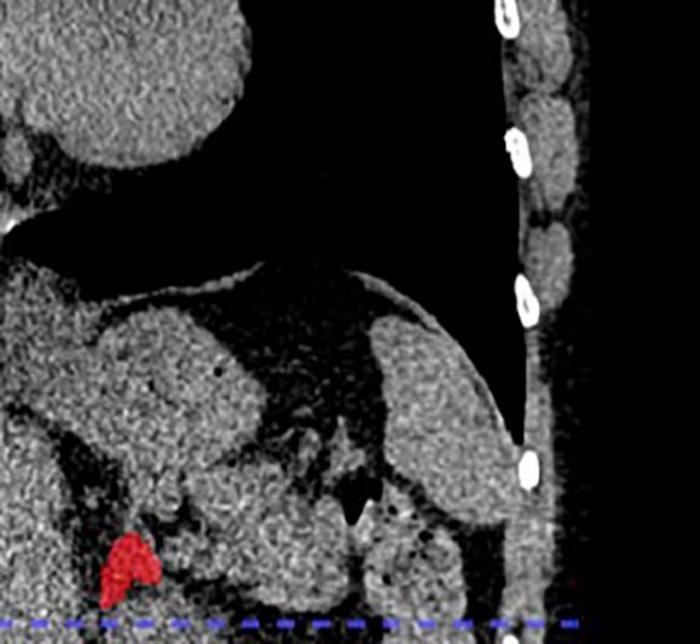

Y es que un equipo de investigadores liderado por la doctora Elena Ghotbi, del Johns Hopkins University School of Medicine, en Estados Unidos, entrenó un modelo de aprendizaje profundo para medir el volumen de las glándulas suprarrenales a partir de tomografías de tórax ya realizadas.

Dado que cada año se realizan decenas de millones de estas tomografías, la técnica tiene el potencial de aplicarse de forma masiva sin necesidad de nuevas pruebas. Gracias a este enfoque, se puede aprovechar información existente para evaluar la ‘carga biológica’ del estrés de forma objetiva.

El indicador, llamado Índice de Volumen Suprarrenal (AVI, por sus siglas en inglés), se define como el volumen de las glándulas suprarrenales dividido por la estatura al cuadrado.